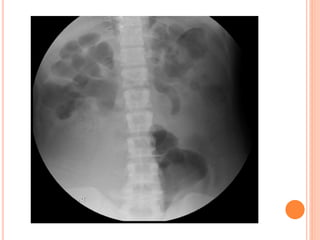

 The preliminary kidney,

ureter, bladder (KUB)

radiograph is an

indispensable part of

the sequence.

PLAIN RADIOGRAPHY(UTP)

- from the suprarenal

region to a level below

the symphysis pubis.

- The patient should void

immediately prior to

examination.

- may require additional

images

KUB

KUB ANALYSIS

 Musculoskeletal: evaluate all bone elements.

 Psoas muscle margin: straight, convex or absent.

 Intestinal gas: overlap, displaced.

 Kidneys

 Calcifications: overlying the UT or outside.

 Gas shadow: abnormal air at UT.